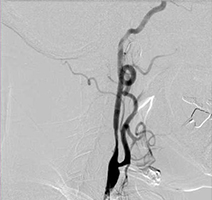

53歳女性、左舌咽神経痛

[画像所見]

-

頭部MRI -

頭部造影三次元CT

左後下小脳動脈が左舌咽神経を圧迫していたために左咽頭部を中心に激しい痛みが生じていました。

[術後画像所見]

術前造影三次元CT -

術後造影三次元CT

左後下小脳動脈(黄色矢印)は術後に本来の位置から移動している。舌咽神経への血管圧迫が解除されたため、術後に患者様は舌咽神経痛が消失した。